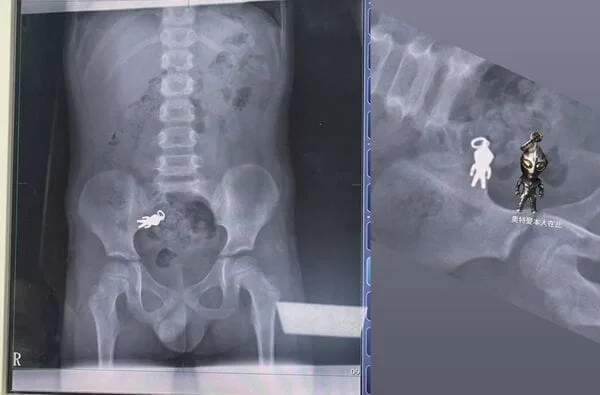

7-Year-Old Accidentally Swallows Ultraman Keychain—X-Ray Shows the Hero Intact

The X-Ray That Made Everyone Smile 😄📸

Rushed to Luodong Boai Hospital in Yilan, the boy received an X-ray that literally captured Ultraman in full form — about 2.8 cm by 1.4 cm — hanging out in his small intestine, still looking heroic. Dr. Xie Jintong (謝錦桐) reassured the family the little keychain was moving along with the bowels just fine, and the boy was perfectly healthy. Talk about a superhero with a safe passage!